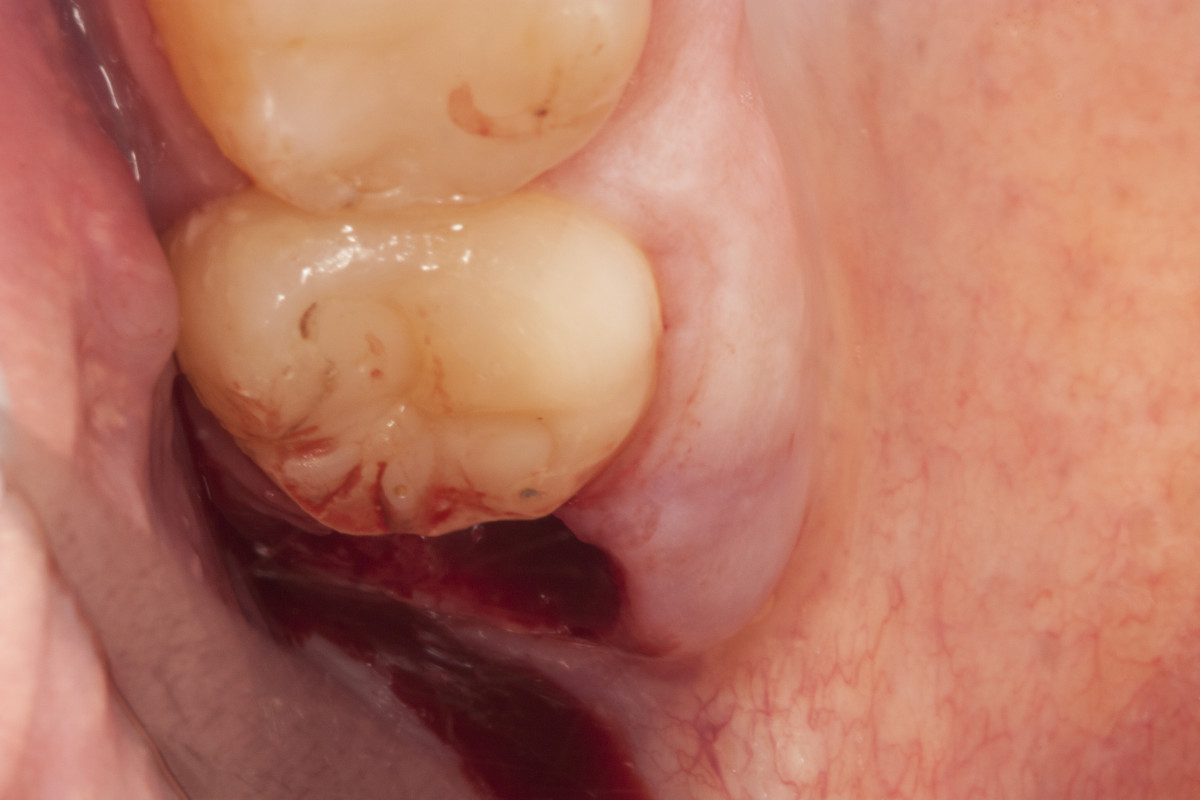

„Pacjent, który się zgłosił z dolegliwościami bólowymi górnej lewej szczęki, miał charakterystyczne objawy dla zapalenia ozębnej. Dzięki wykonaniu diagnostyki radiologicznej (zdjęcie pantomograficzne), ujawniono istnienie dziewiątego zęba, który był dodatkowo obciążony okluzyjnie. Pacjent miał otwarty zgryz – w momencie, kiedy zamykał zęby kontaktował się tylko na zębach trzonowych. To wszystko powodowało, że główny nacisk zębów był na tą malutką stożkową dziewiątkę. Przeciążenie tego zęba spowodowało to, że związanie włókien kolagenowych z podłożem kostnym osłabiło się, powstała kieszeń dziąsłowa i kieszeń kostna. To wszystko było przyczyną silnych dolegliwości bólowych o charakterze periotonditis, czyli zapaleniu wzdłuż calej długości ozębnej.

Pomimo, że ten ząb umieszczony w guzie szczęki, w miejscu bardzo odległym, niewidocznym i pacjent nie miał świadomości, że ma ząb dziewiąty, to zabieg był dość prosty, nie sprawiający kłopotów i nie wystąpiły żadne komplikacje.” –